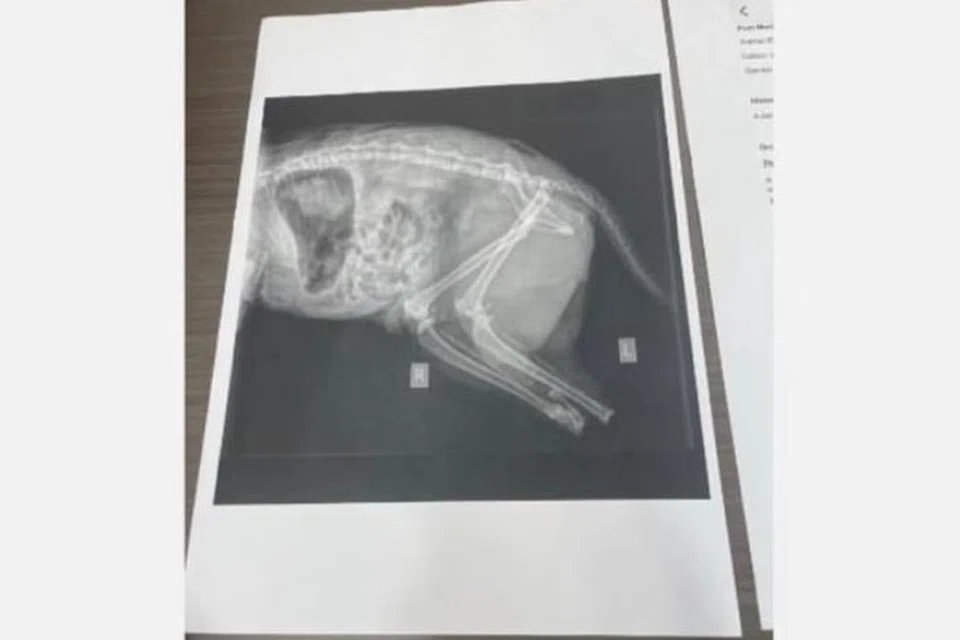

Namun laporan itu ditolak beberapa aktivis haiwan, doktor veterinar dan badan bukan kerajaan (NGO) penyelamat dan pencinta haiwan yang mendesak siasatan lebih terperinci, berikutan hasil laporan perubatan mengesahkan kucing berkenaan mati dengan kesan kaki dipotong dengan senjata tajam.